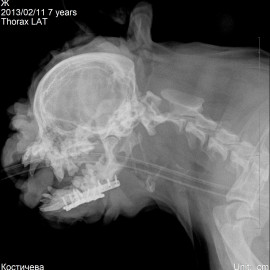

В другой клинике был поставлен диагноз: перелом тела нижней челюсти правой и левой стороны. Была проведена операция: остеосинтез нижней челюсти.

Снимок 3-4 после операции.